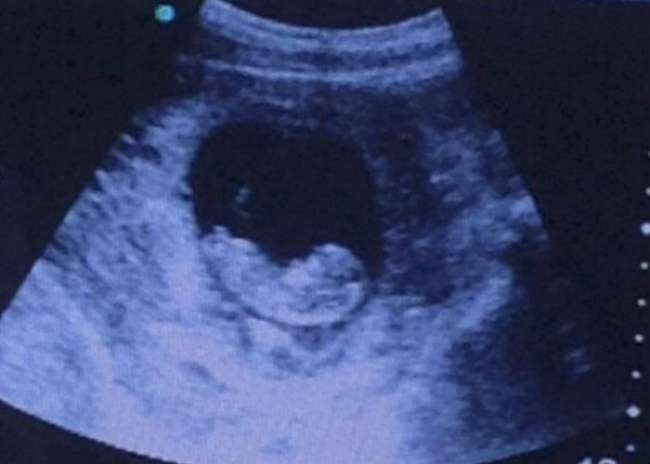

Een ‘griezelige’ echo - waarbij het lijkt of er een demon ‘waakt’ over een foetus in de baarmoeder - gaat momenteel viraal op het internet. De echo die werd geplaatst door een anonieme Imgur-gebruiker is inmiddels een miljoen keer bekeken in twee dagen.

De mensen die de echo gezien hebben, hebben zo allemaal hun eigen interpretatie van wat er nu daadwerkelijk te zien is op de foto. De echo laat een foetus zien van rond de acht tot tien weken oud, met naast de baarmoeder iets wat lijkt op een figuurtje met een dreigend gezicht en een naakt lichaam.

De Imgur-gebruiker schreef erbij: ‘Echo van een vriend. Als je het ziet…’ Gebruiker JosePhINCH was één van de eersten die het griezelige gezicht spotte: 'Er zit een demon rechts', terwijl Manshottothemoon zei: ‘Ziet niemand anders die demon rechts?’. Echter, andere gebruikers interpreteerden het figuurtje anders. Ene Jackbos schreef: 'Hindoeïstische godin aan de rechterkant van het beeld.' Subtlemrs zei: 'Ik zie een vriendelijke zeemeermin. Iedereen ziet een demon. We zijn allemaal raar. '

Toen honderden mensen naar de site gingen om meer informatie krijgen, moest de degene die de foto gepost had wel even een update geven. Luigivampa-over9000 verklaarde: 'Alles is prima nu. De baby was twee maanden te vroeg geboren. Ze vroegen degenen die de echo maakten wat dat nu was, maar men had niet echt een antwoord behalve dat ze zoiets nog nooit eerder gezien hadden. Best een interessant verhaal met een passende foto...’